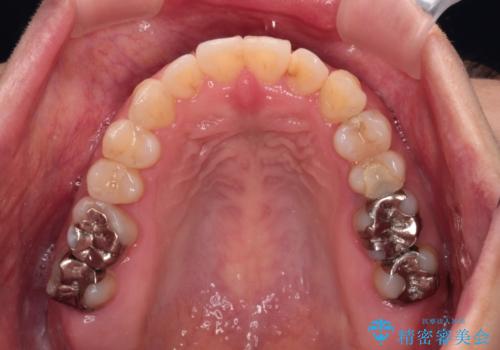

- 前歯の捻れを気にして来院された患者様です。

上顎前歯が捻れて前方に飛び出しており、下顎前歯もそれに沿うようにデコボコとなっていました。

IPR(歯と歯の間を削る処置)によりスペースを獲得して上下前歯のデコボコを改善し、インビザラインにて矯正治療を行うこととしました。

捻れていた前歯の形態が、先端が欠けていたり、一部むし歯処置により左右非対称の形態となっていたため、なかなかゴールが定まらず、治療期間がかかってしまいました。